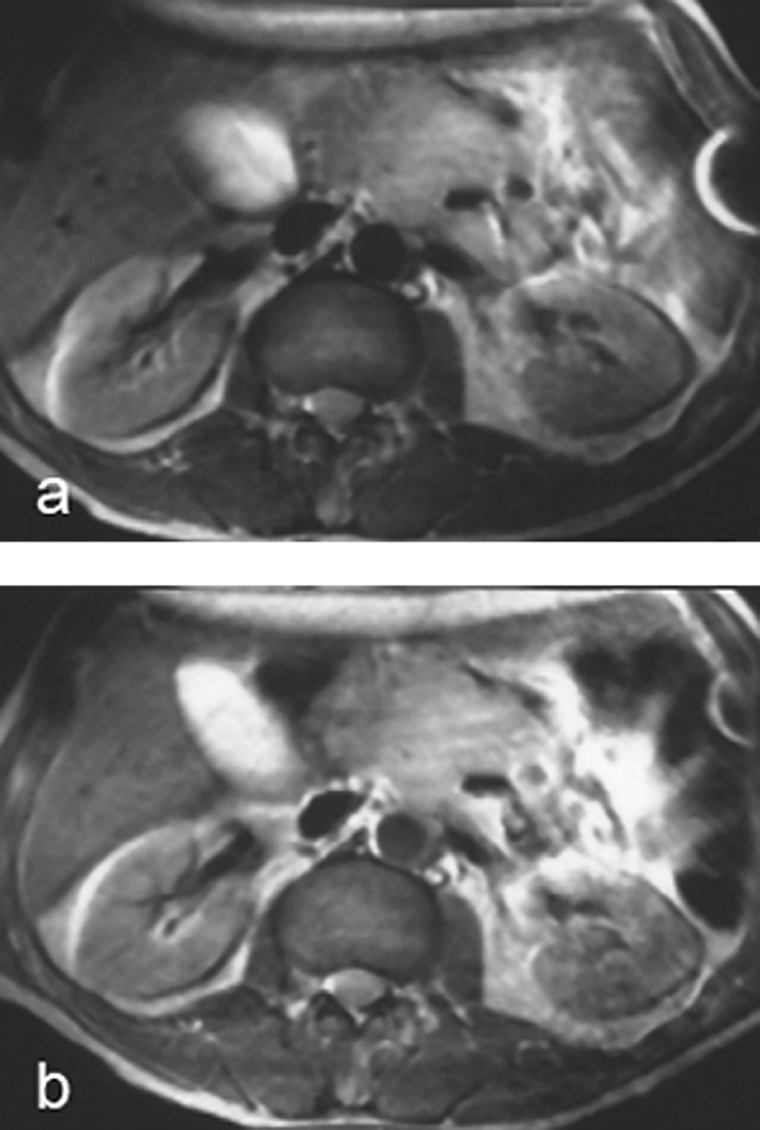

Figura 13-19:

Intermediately weighted images of the up­per abdomen. Recurrent mesenteric tumor.

(a) plain; (b) after ingestion of a negative oral contrast agent. On the enhanced ima­ge, the contour of the tumor is well de­li­ne­ated from the neighboring liver and in­tes­ti­nes.

Artifact created by ECG lead in the left ab­do­mi­nal wall.